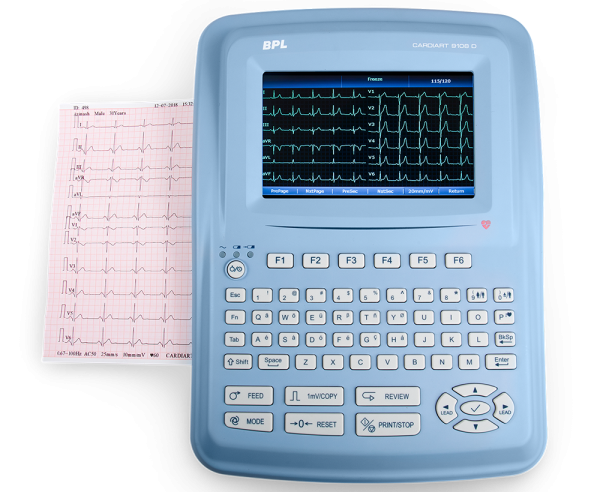

Bionet CardioTouch 3000 12 Channel ECG Machine

Bionet CardioTouch 3000 12 Channel ECG Machine

Pulsemed UK Cardiosense 12

Pulsemed UK Cardiosense 12

BPL ECG MACHINE 12 CHANNEL

BPL ECG MACHINE 12 CHANNEL

DAWEI 12Channel ECG Machine

DAWEI 12Channel ECG Machine

.jpeg) Comen – 12 Channel ECG Machine, CM1200

Comen – 12 Channel ECG Machine, CM1200

CardioCare 2000 ECG

CardioCare 2000 ECG

Philips ECG Machine

Philips ECG Machine